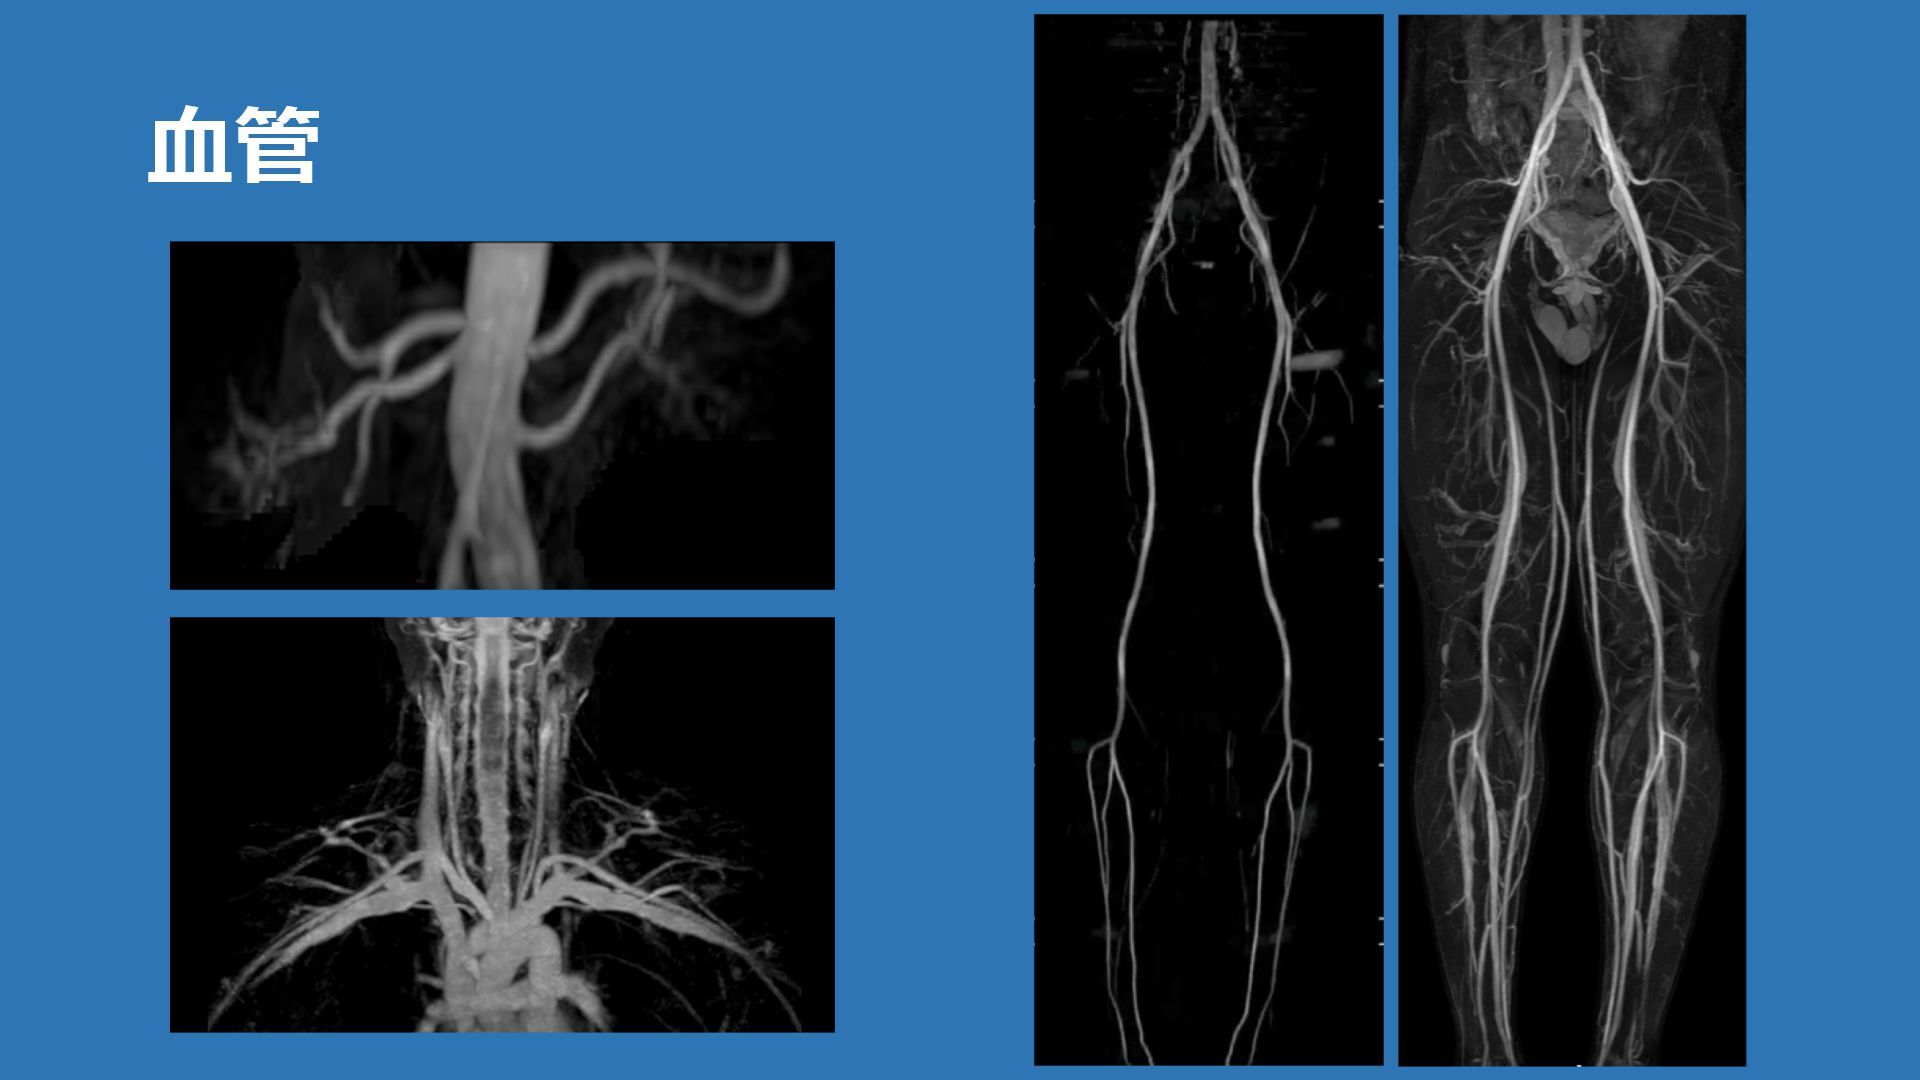

⾎管